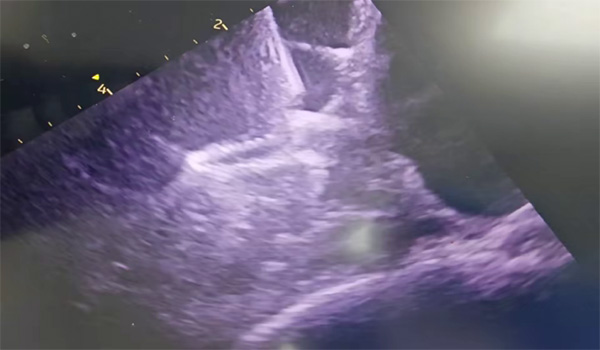

(超声检查)

植入过程:释放封堵盘后造影可见下缘存在少量残余分流,通过超声观察为靠近二尖瓣位置贴靠不佳,但术中评估钢缆拉力明显,预估释放后能够有效贴合,牵拉15s无位移,可以释放。

通过超声可见封堵器外盘形态良好,未见明显残余分流;可再行房间隔缺损封堵术。